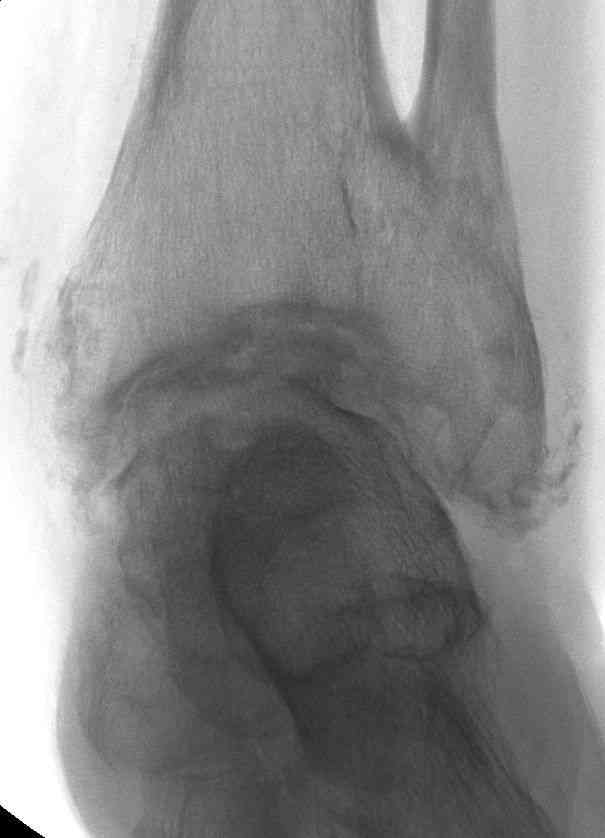

Эндопротезирование или артродезирование ?К нам обратился пациент 73 лет с жалобами на боли и деформацию в области левого голеностопного сустава. В анамнезе: в 1980 году перелом обеих лодыжек с вывихом стопы кнаружи. Лечился консервативно: одномоментная репозиция переломовывиха в левом голеностопном суставе с трансартикулярной фиксацией голеностопного сустава спицами Киршнера через пяточную, таранную, большеберцовую кости. Накладывалась гипсовая иммобилизация. Даная манипуляция осложнилась нагноением с развитием гнойного артрита. Были удалены спицы, сустав со слов больного, промывался растворами, но не вскрывался, получал антибиотики. Гнойный процесс был купирован, и рецидива с тех пор не было.Об-но: Левый голеностопный сустав деформирован за счет разрастания костной ткани и отечности мягких тканей. Левая стопа с вальгусной установкой, практически отсутствуют все своды левой стопы (стопа плоская). Полный объем движений в левом голеностопном суставе максимум достигает 15 гр, движения стопы в основном за счет подтарнного сустава. Пальпаторно область голеностопного сустава не столь болезненна, как болезненна область подтаранного сустава и область таранно-ладьевидного сустава.После изучения объективного статуса, анамнеза, рентгенснимков, больному предложен был трехсуставной артродез, так-как мы сочли это наиболее приемлемым в данном случае. Но больной отказывается от данной операции и настаивает на эндопротезировании левого голеностопного сустава. Во первых, наше отделение не имеет опыта в эндопротезиовании голеностопного сустава. Во вторых, нам кажется, что трехсуставное артродезирование в данном случае наиболее подходящее. Причиной тому, на наш взгляд, выраженная деформация левой таранной кости, как следствие аваскулярного некроза, и то что болит не голеностопный сустав в данном случае ( хотя в нем и ограничено движение), а подтранный и таранно-ладьевидный суставы и то что эндопротезирование одного голеностопного сустава не решит проблем в подтаранном, ладьевидно-таранном сочленениях. Наши доводы оказались безуспешными, а так как пациент является ученным, требовал доказательной базы наших умозаключений. Ваше мнение по данному случаю, и мы были бы благодарны, если у кого то есть материал по данной теме или есть ссылки. Заранее благодарны всем, кто примет участие в обсуждении данной темы.